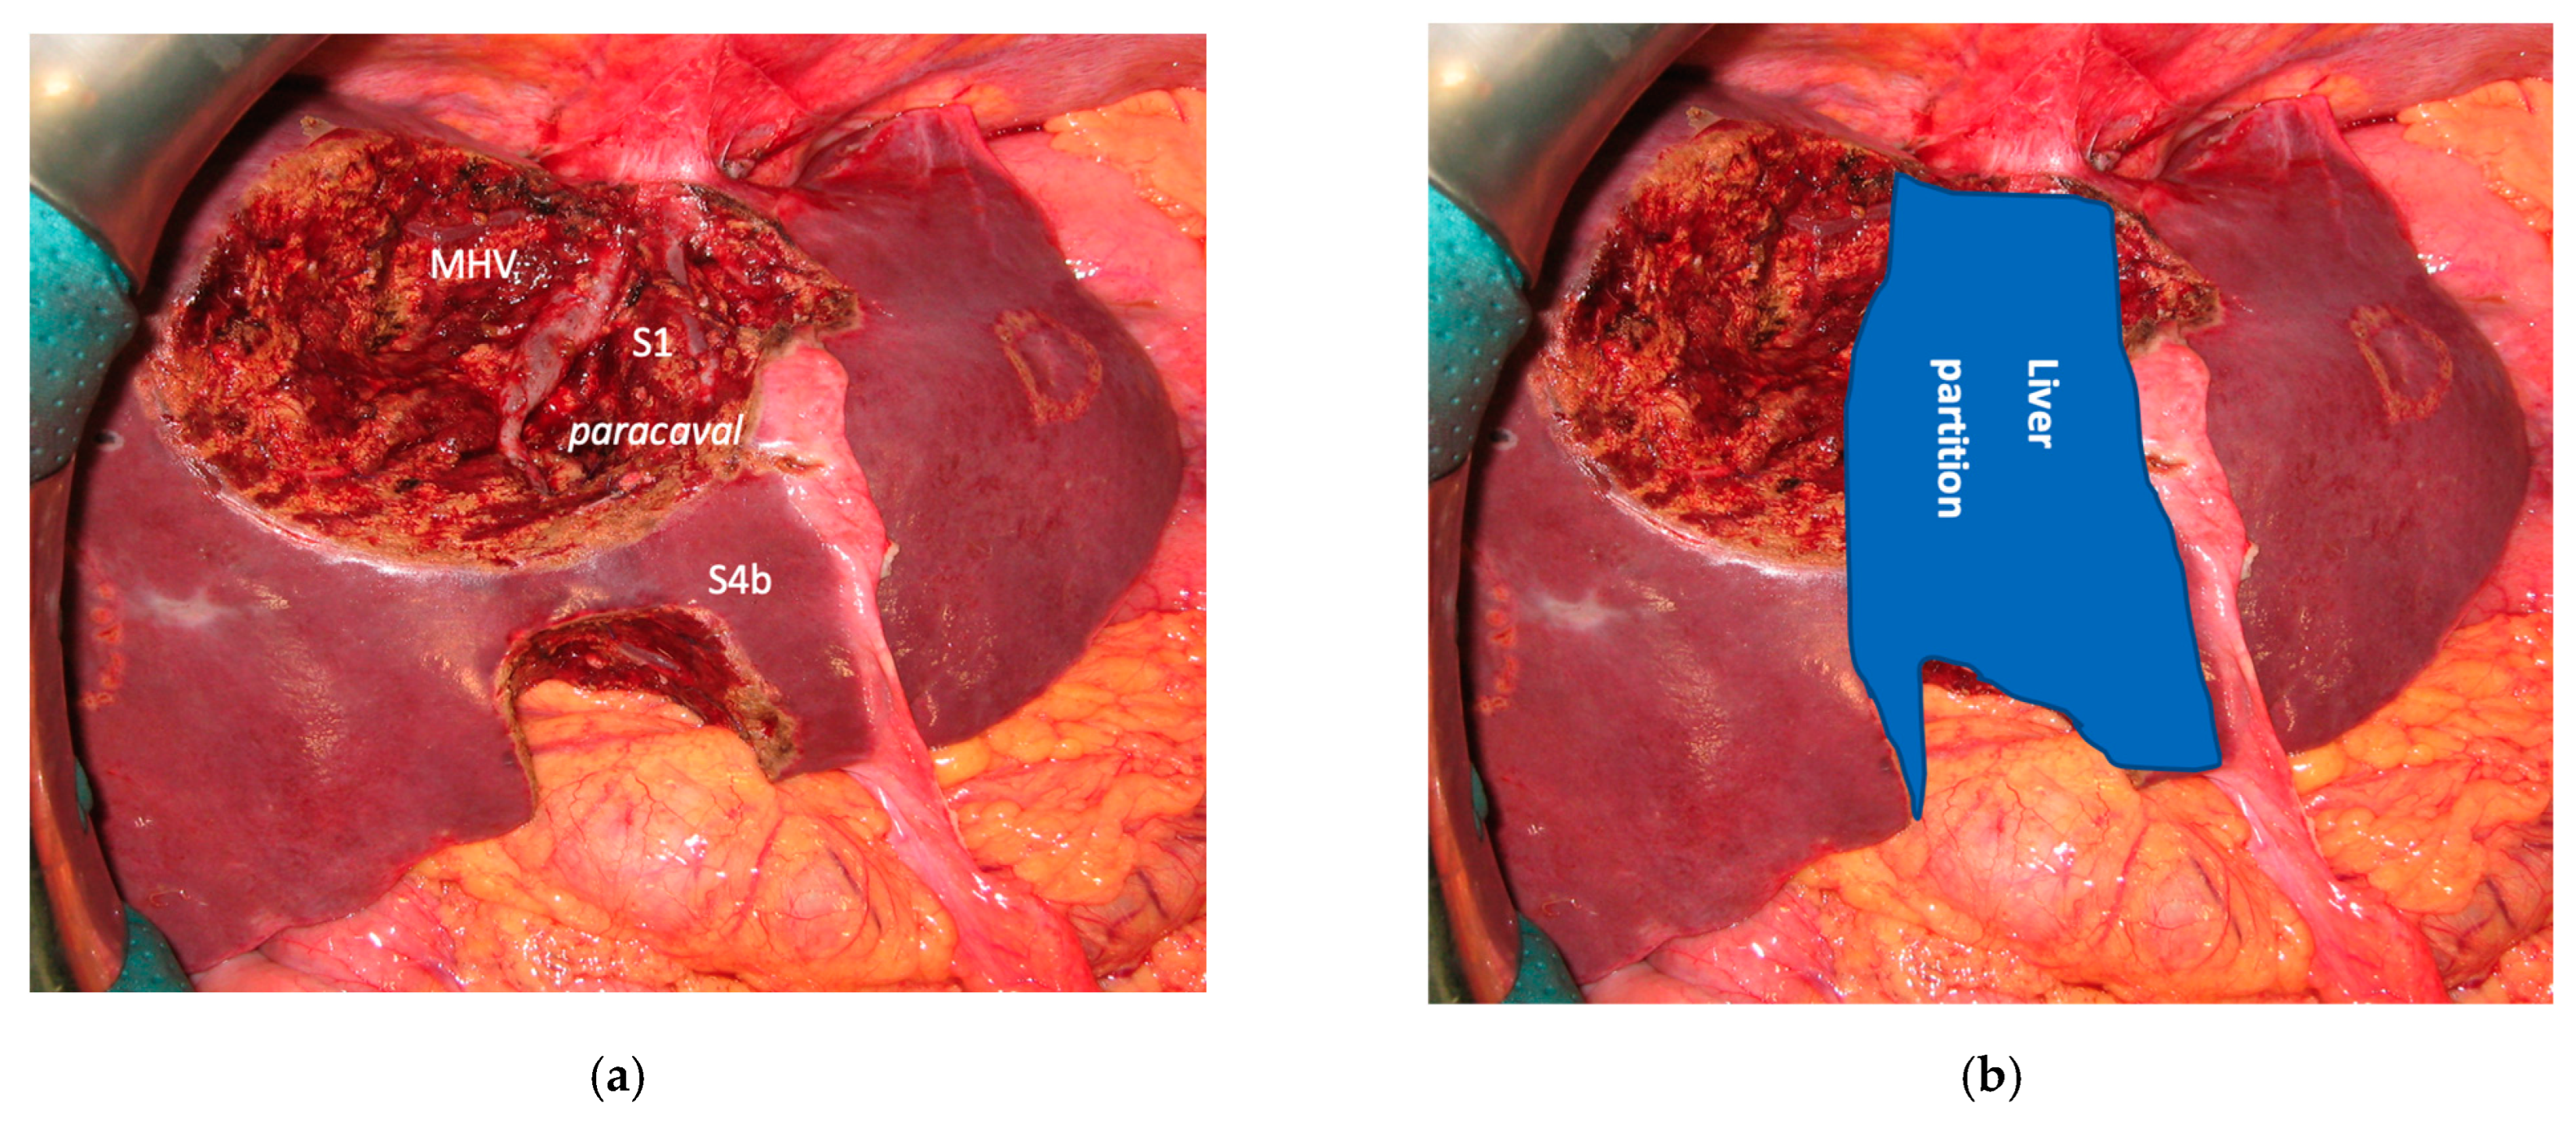

Figure 4. Intraoperative field images of a vessel-guided mesohepatectomy of S1/S4 en-bloc with MHV for liver partition (MLP). MLP is a minor resection (less than 3 adjacent liver segments) inducing a major hepatic scaffold modification transforming the liver into a paired organ. (a) Liver transection lines (yellow dotted lines). (b) Intraoperative view of the two livers. (c) Surgical specimen of S4/S1 en-bloc with MHV corresponding to a volume of 205 mL. Abbreviations: MLP: mesohepatectomy for liver partition; MHV: middle hepatic vein; RHV: right hepatic vein; S: segment; GP: glissonean pedicle; UP: umbilical portion.

3.1. MLP

In all 15 cases planned vessel-guided MLP was successfully carried out. For the surgical approach, a J-shaped laparotomy was used in 13 cases and the xipho-pubic incision in two; no thoraco-abdominal incision was needed. In two cases of MLP performed as the first stage of ALPPS, liver partition was obtained with a single transection line: in one case (FLR = S2/S3/S4b) between a part of S4b and S5 since S4a/S1 were resected in previous e-OSH, in the other case (FLR = S4/S2/Spiegel lobe) the single transection line preserved part of S4a/S4b and the Spiegel lobe. In 11 cases liver partition was obtained with a minor mesohepatectomy: in one case with resection of S4a/S1 partially extended to S5 preserving S4b, in two cases with resection of S1/S4 preserving the Spiegel lobe, in one case with resection of segments S5/S8 extended to the caudate processus of S1 preserving the Spiegel lobe and paracaval portion of S1 and in the other seven cases with anatomic resection of S1/S4 (see Figure 4).

Liver partition was obtained with a major mesohepatectomy in two cases with anatomical resection of S1/S4/S8 (en-bloc with biliary tree in one, see Figure 5).

Complete separation of left and right liver is achieved performing a mesohepatectomy involving segments S4 and/or S5/S8 en-bloc with S1 or the paracaval portion only and/or the caudate processus. At the end of liver partition, two independent livers are obtained, with regular inflow and outflow and biliary drainage. The confluence between first-order GPs is always exposed completely (vessel-guided hepatectomy) and the middle hepatic vein (MHV) is usually resected.